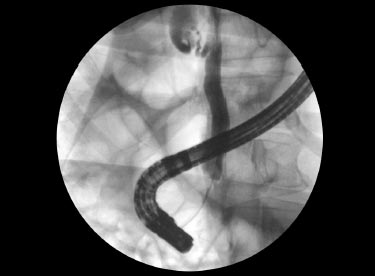

Ultrasonography is a simple, low-cost, easily available, and noninvasive test that allows easy identification of extrahepatic dilatation of the biliary tree. Computed tomography (CT), magnetic resonance cholangiopancreatography (MRCP), and endoscopic retrograde cholangiopancreatography (ERCP) (Fig. 1) are better to reveal hepatic morphology and potential obstructions.

FIG. 1: ERCP—cholangiogram showing a dilated CBD seen in extrahepatic cholestasis.

(CBD: common bile duct; ERCP: endoscopic retrograde cholangiopancreatography)